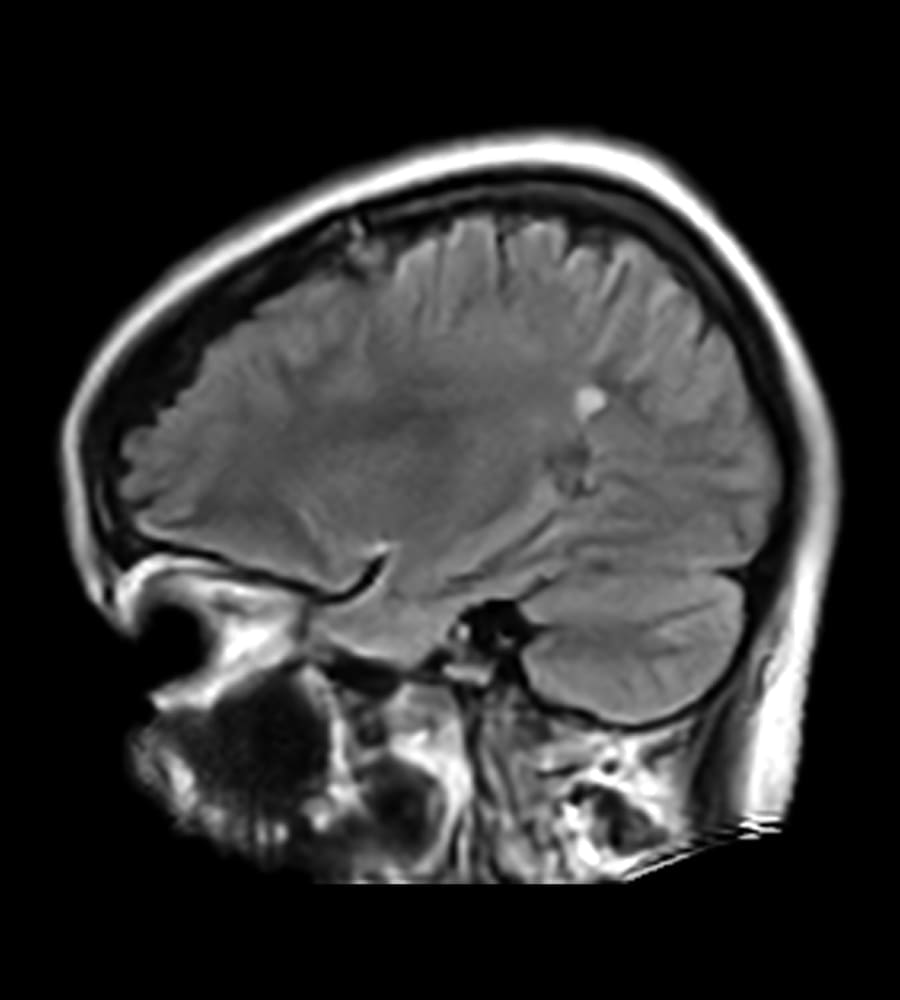

Clinical Images

Clinical case types: Headache, Migraine, Multiple Sclerosis, Micro Vascular Disease and Tumor Routine Follow-up.